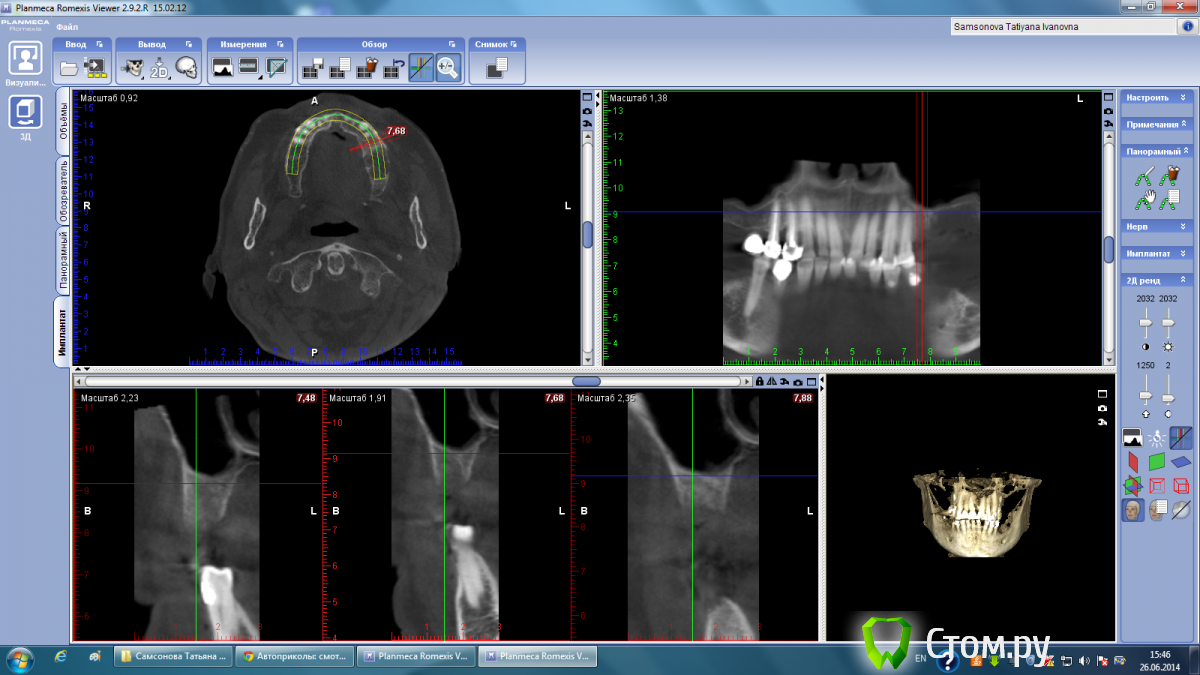

Тимур86 Опубликовано 26 июня, 2014 Поделиться Опубликовано 26 июня, 2014 пациентка пожилого возраста,хочется имплантов... Ссылка на комментарий

Mane Опубликовано 26 июня, 2014 Поделиться Опубликовано 26 июня, 2014 Вопрос автору - какие задачи вы ставите перед собой у этого пациента. Совершенно видно что нужен синус. Как вы считаете в пожилом возрасте не достаточно синуса и десны на втором этапе. И керамика розовая или чуть большеватые коронки. Оправдан здесь огород с костной пластикой. Если вертикалить то ламинаты или сетка или тайтэниум реинфорсд мембрэйн. Самое простое решение конечно же с сеткой. Но самые высокие риски прорезывания (у меня). Ждем ваши ответы. 1 Ссылка на комментарий

Тимур86 Опубликовано 26 июня, 2014 Автор Поделиться Опубликовано 26 июня, 2014 Ждем ваши ответы.согласен совершенно,естественно хочется минимизировать объемы костной пластики(и не только у пожилых пвциентов)но не снизит ли срок службы имплантов такое соотношение имплант/коронка в "псевдокости"? Ссылка на комментарий